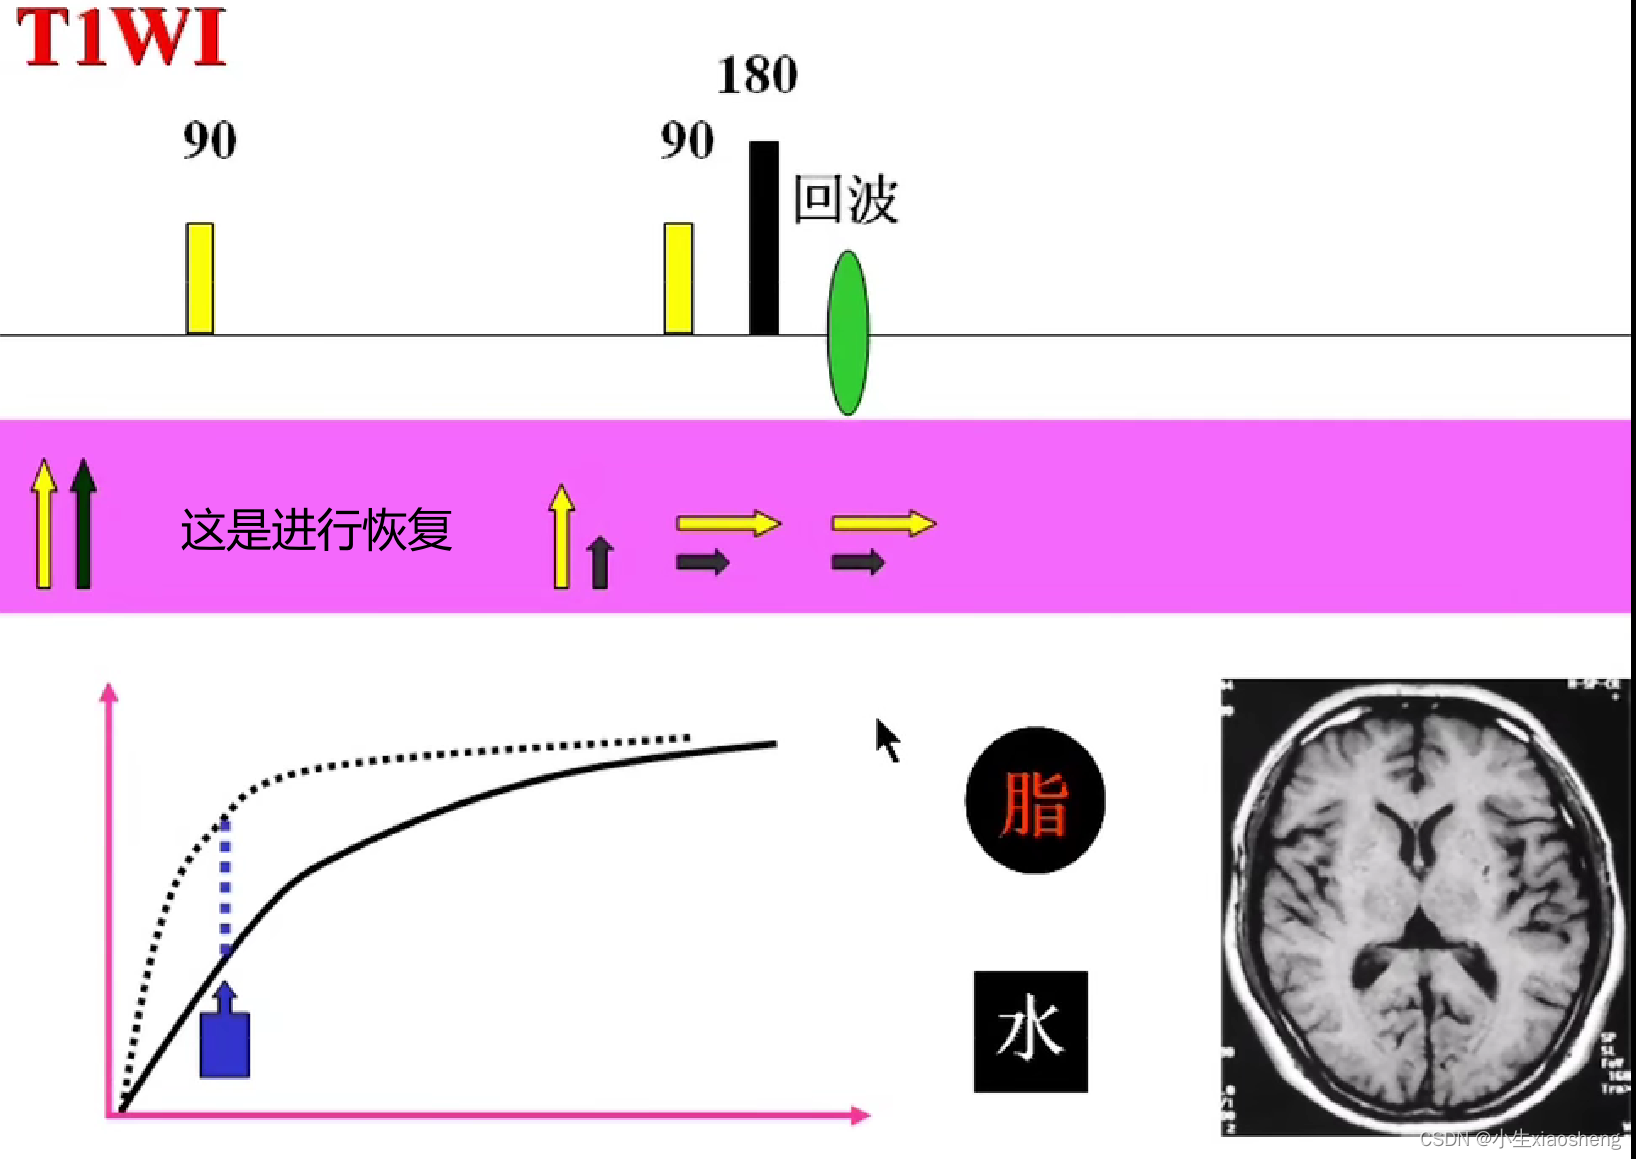

选择合适长的TE获得最好的T2对比:一般TE选择两种组织生物T2值附近可获得最好的T2对比。

选择合适短的TR获得最好的T1对比:一般TR选择两种组织生物T1值附近可获得最好的T1对比。